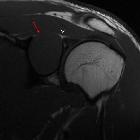

Peripheral

schwannoma mimicking a bone tumour. Isointense well-defined mass with epicentre in the spinoglenoid notch (red arrow). Note the close relationship with the suprascapular nerve (white arrow).